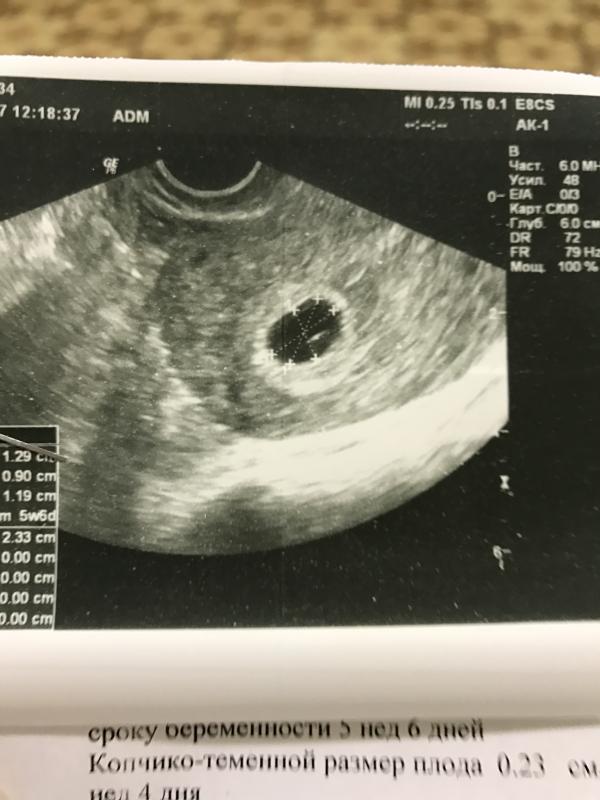

На УЗИ сказали беременность есть, маточная, сердечко бьётся😊всё по сроку😊

Чёрная точка на узи - это моя ляля😊очень надеюсь, что всё обойдётся и мы будем расти дальше!😊